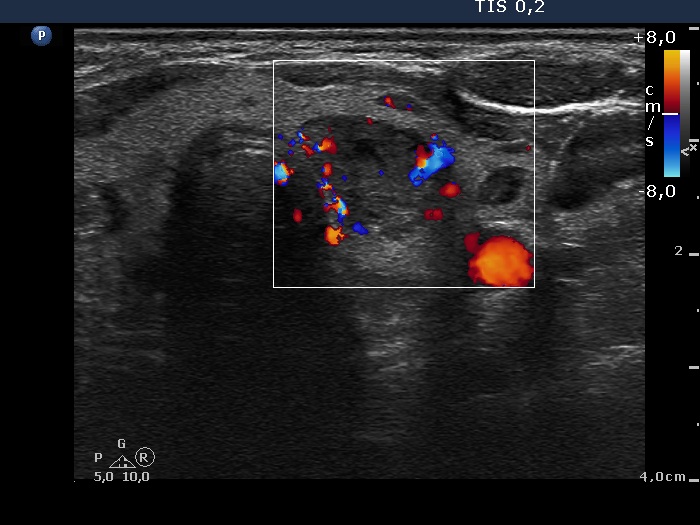

Differential diagnostic of cystic lesions - table 1

Different types of cystic nodules are presented in this table.

There are two seemingly pure cysts in the left upper image. However, longitudinal scan (left lower image) discloses that the dorsal lesion is in fact an eccentric type mixed nodule with almost 50 percent of solid part. There is another seemingly pure cyst in the ventral part of the lobe. We only mention here that without aspiration we cannot define pure cysts. In many cases solid part will appear only after aspiration of cystic fluid.

The largest nodule presented in the right column is best to held as a solid nodule because the proportion of cystic fluid is less than 10 percent.